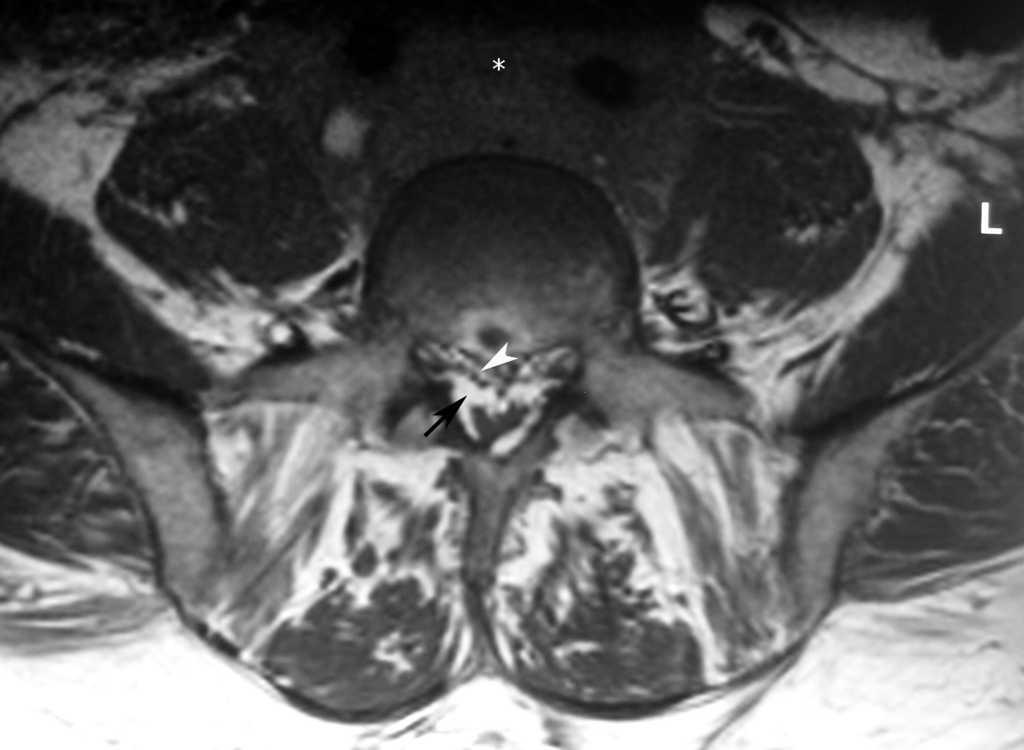

Se realizó una resonancia magnética (RM) de la columna lumbar (sin y tras contraste intravenoso) y se observaron, además de la masa retroperitoneal que comprimía la VCI, unas imágenes puntiformes y lineales hipointensas en todas las secuencias que ocupaban el espacio epidural adyacente al muro posterior de las vértebras lumbosacras, que se extendían a través de los agujeros de conjunción hacia las partes blandas perivertebrales (figs. 1-3). Esta alteración correspondía a estructuras vasculares dilatadas dependientes del plexo venoso epidural vertebral.

Fig. 1. Resonancia magnética ponderada en T1 (A) sagital línea media, (B) parasagital y (C) axial. (A) Aumento de la grasa epidural que comprime el saco tecal debido a lipomatosis (flecha); (B) imágenes hipointensas puntiformes en el espacio epidural anterior que corresponden a estructuras vasculares dilatadas del plexo lumbosacro (flechas); (C) masa retroperitoneal que engloba grandes vasos (asterisco). Se objetiva la presencia de lipomatosis (flecha blanca) y las estructuras vasculares dilatadas (punta de flecha blanca).